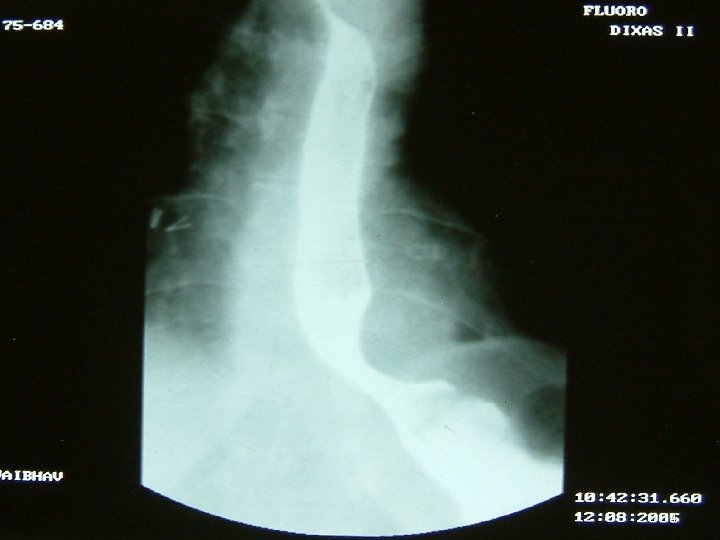

Investigations • • • Chest X Ray USG CECT EUS Ba Swallow 3

4

5

6

7

8